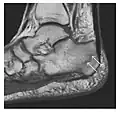

Proximal femoral fractures usually occur in osteoporotic patients, and their signs include subtle neck angulation, trabecular angulation, and subcapital impaction line. A frog-leg lateral view may be helpful if the greater trochanter is short enough. However, positioning can be difficult because of hip pain. In patients with strong suspicion of proximal femoral fracture and negative radiographs, MRI limited to coronal T1 W images and scintigraphy can be highly valuable (Figures 13 and 14). Such an option, with limited examination time, is cost-effective and allows reliable exclusion or confirmation of the diagnosis, preventing an unnecessary stay at the hospital or delayed treatment. Moreover, MRI helps to detect soft tissue abnormalities which are more frequently seen in femoral, acetabular, and pubic injuries than sacral lesions. Concomitant fractures are also frequently seen in typical pelvic sites.[1]

Figure 13: Partial osseous avulsion of the gluteal muscles at the greater trochanter in a 59-year-old man who presented with the right hip pain without a history of trauma. Lauenstein view and anteroposterior and radiographs (not shown) did not show an obvious fracture line or disruption of bony contours in the acetabulum or the right femoral neck. (a) Coronal T1-weighted MRI displays an incomplete fracture line extending partially from the greater trochanter (arrow). (b) Coronal short tau inversion recovery MRI shows heterogeneous hyperintensity in the same region (arrow) as well as hyperintensity within the gluteus medius and minimus muscles (arrowheads) consistent with tissue edema and hematoma.[1]

Figure 14: Subcapital insufficiency fracture in a 55-year-old man with a left hip pain without a history of trauma. Anteroposterior and Lauenstein view radiographs centered on the left hip do not show an obvious fracture line, but mild acetabular osteophytosis was noted consistent with hip osteoarthritis (not shown). (a) Coronal T1-weighted MRI shows a linear low-signal band through the femoral neck corresponding to a fracture line (arrowheads). (b) Bone scintigraphy shows focal uptake (arrow) corresponding to the fracture.[1]